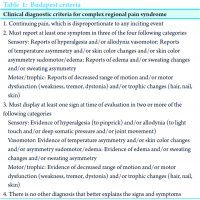

The patient returned for follow-up 3 months later stating that she was somewhat improved. She still complained of intermittent swelling of the right thumb and index finger. On physical exam, the tenderness over the right thumb was unchanged. However, the range of motion of the right thumb and index finger had increased. Gabapentin and range of motion exercises were continued. She was then lost to follow-up but did return 7 months later. At this point, she reported no improvement in pain of the right thumb or range of motion of right index finger and thumb. In the interim, she discontinued taking gabapentin because it was not helpful. The physical exam of the right hand was significant for trophic changes in the right index finger and thumb, with decreased range of motion and a significant decrease in skin wrinkling also noted (Fig. 2). She was again prescribed gabapentin and instructed to continue range of motion exercises at home. The patient was again lost to follow-up but was contacted by telephone approximately 21 months after the initial presentation. She stated that she felt unchanged with regard to hand swelling and pain but does believe the Neurontin is helpful and continues to take 300 mg 3 times per day.

Our case presentation brings forth the question of whether the patient suffered CRPS triggered by the shingles outbreak or if this was simply a case of post-herpetic neuralgia with CRPS-like symptoms. A prospective randomized study by Berry et al. demonstrated that CRPS-like symptoms were found exclusively in patients whose herpetic rash extended into the affected extremity. Further, that study found that the more distal the herpetic rash on an extremity, the more severe and the longer the clinical course. In that series of 25 patients, no subject progressed to severe CRPS with the associated symptoms of sweating, hair and nail changes, severe dystonia or joint deformity [2]. In our patient, we noted similar signs and symptoms of pain, asymmetrical skin discoloration, edema, and decreased range of motion to the thumb and index finger. However, at no time did the patient demonstrate increased perspiration, hair and/or nail changes or joint deformity to the hand (Fig. 1 and 2) that could be associated with CRPS. This case also highlights the difficulty in making the clinical diagnosis. Other common conditions, such as rheumatoid arthritis and osteoarthritis, may also present with hand pain associated with decreased range of motion. In this case, we used the Budapest criteria to make the clinical diagnosis of CRPS (Table 1) [3]. The diagnosis may have been missed if not for using the diagnostic criteria. A delay in diagnosis would have led to a delay in treatment with possibly an even longer course of recovery for the patient. Our primary modality of treatment planned for this patient was to be an extended physical therapy regimen. There is evidence to suggest that this modality is helpful in decreasing the symptoms of CRPS [4, 5]. Physical therapy using graded motor imagery for an extended period up to 1 year may be required [4]. Our patient had a barrier to extended physical therapy due to insurance limitations. This is an ever increasing issue, and patients, as well as physicians, may need to work with third-party payers to extend access to physical therapy longer than a few visits over a few weeks.